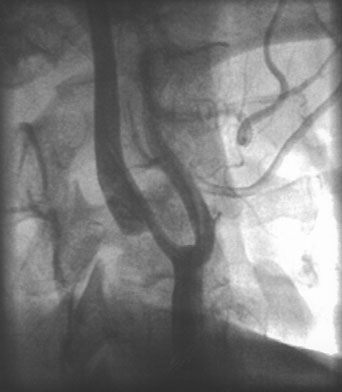

As diffusion-perfusion MRI and other techniques to quantify blood flow, such as perfusion CT and xenon-CT, become more widely available, clinicians will be better equipped to estimate the relative benefits and risks of thrombolysis, based more on physiologic data than rigid time constraints. Patients with large areas of penumbra tissue would benefit most, while those with large tissue volume with blood flow under 10 mL per 100 g/min would not benefit and may be at increased risk for hemorrhage. A recent report utilizing diffusion-perfusion MRI to guide thrombolysis with desmoteplase allowed the safe and apparently efficacious administration of this thrombolytic agent up to 9 hours after the onset of ischemia.45 Figure 1 exemplifies the use of diffusion-perfusion MRI in acute stroke treatment. Ideally, multimodal testing of the parenchyma to exclude hemorrhage, a viability study to determine the amount of salvageable brain, and a vascular study to assess vessel patency would provide the clinician with the information to make rational decisions regarding the need to treat. Magnetic resonance (MRI, diffusion-perfusion imaging, and magnetic resonance angiography [MRA]) and CT technology (with CT perfusion and CT angiography) have the potential to guide this multimodal evaluation.

Fig. 1. An 81-year-old man with atrial fibrillation developed acute onset of left-sided weakness and presented to hospital 3 hours and 40 minutes after onset of symptoms. A: The diffusion-sequence magnetic resonance imaging (MRI), with infracted tissue in the right basal ganglia in white. B: Decreased perfusion in the right middle cerebral artery distribution (white area). Given the relatively small diffusion abnormality and the large perfusion defect, it was decided to proceed with thrombolysis despite the time elapsed.